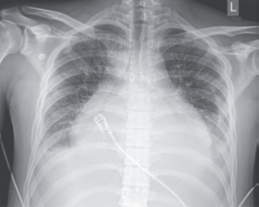

当我们在说梨形心、靴形心、烧瓶心的时候

梨形心、靴形心、烧瓶心丨这也样看平片,

18种不容忽视的X线诊断要点

实践技能辅助检查之普通X线影像诊断-心脏

教你如何理解记忆靴形心,梨形心和普大心